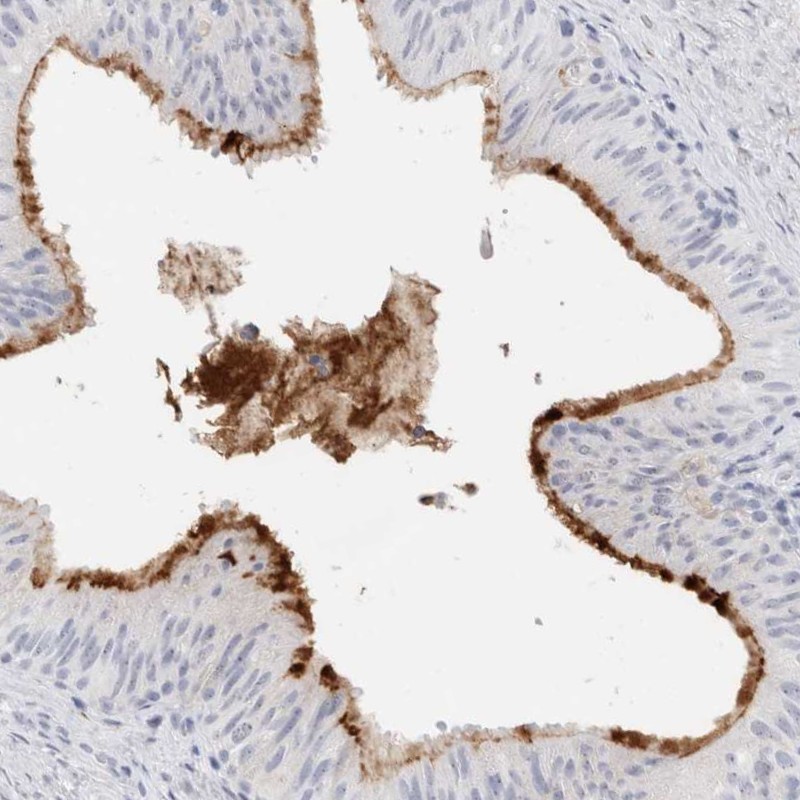

Immunohistochemical staining of human epididymis shows moderate membranous positivity in glandular cells.